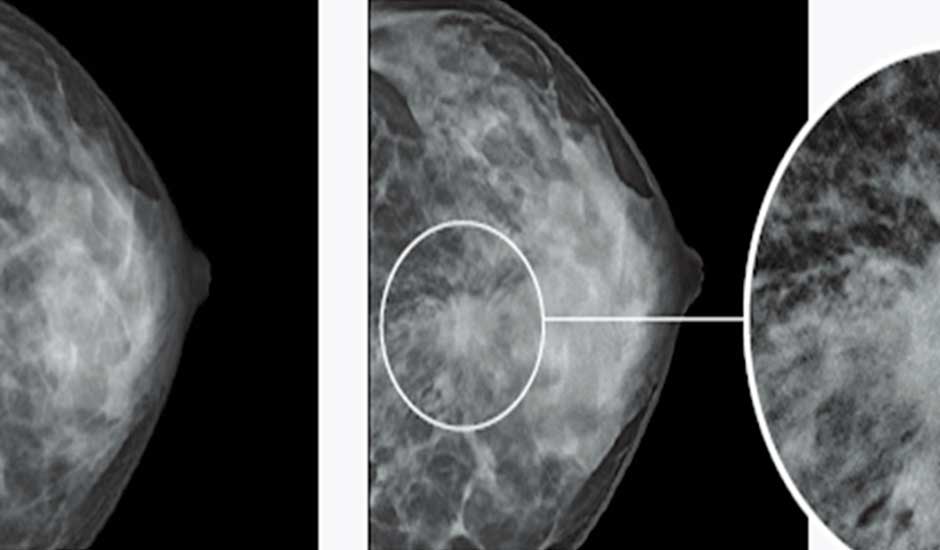

Los investigadores afirman que el programa fue entrenado con decenas de estudios sobre esta enfermedad. Además, también ha observado miles de ‘mamografías‘ provenientes de 60,000 pacientes, por lo que el número total de mamografías asciende a 90,000.

En primera instancia, procuraron identificar patrones repetidos, los cuales muchas veces no son evidenciados por los doctores. Esto es esencial para predecir la enfermedad, y es el campo en donde mejor se comportó esta ‘Inteligencia Artificial‘; pues los resultados han demostrado ser mucho más precisos que los de un humano.

Por esta razón, el equipo encargado confirmó que su proyecto está destinado a detectar la enfermedad lo más antes posible. Hasta el momento, han realizado el logro de detectarlo cinco años antes de los síntomas. Después de todo, el ‘diagnóstico tardío‘ es el peor enemigo del cáncer.